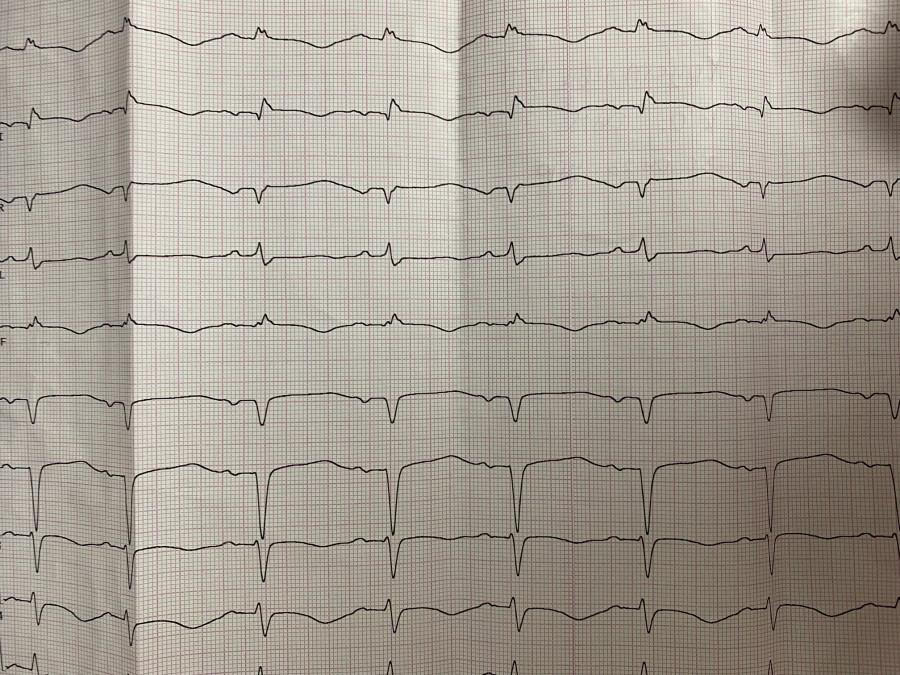

Ускоренный узловой

Обсуждалось здесь https://vk.com/club84409679?w=wall-84409679_13555%2Fall

IMG_4260.jpg

IMG_4260.jpg [ 1.01 MiB | Просмотров: 14296 ]